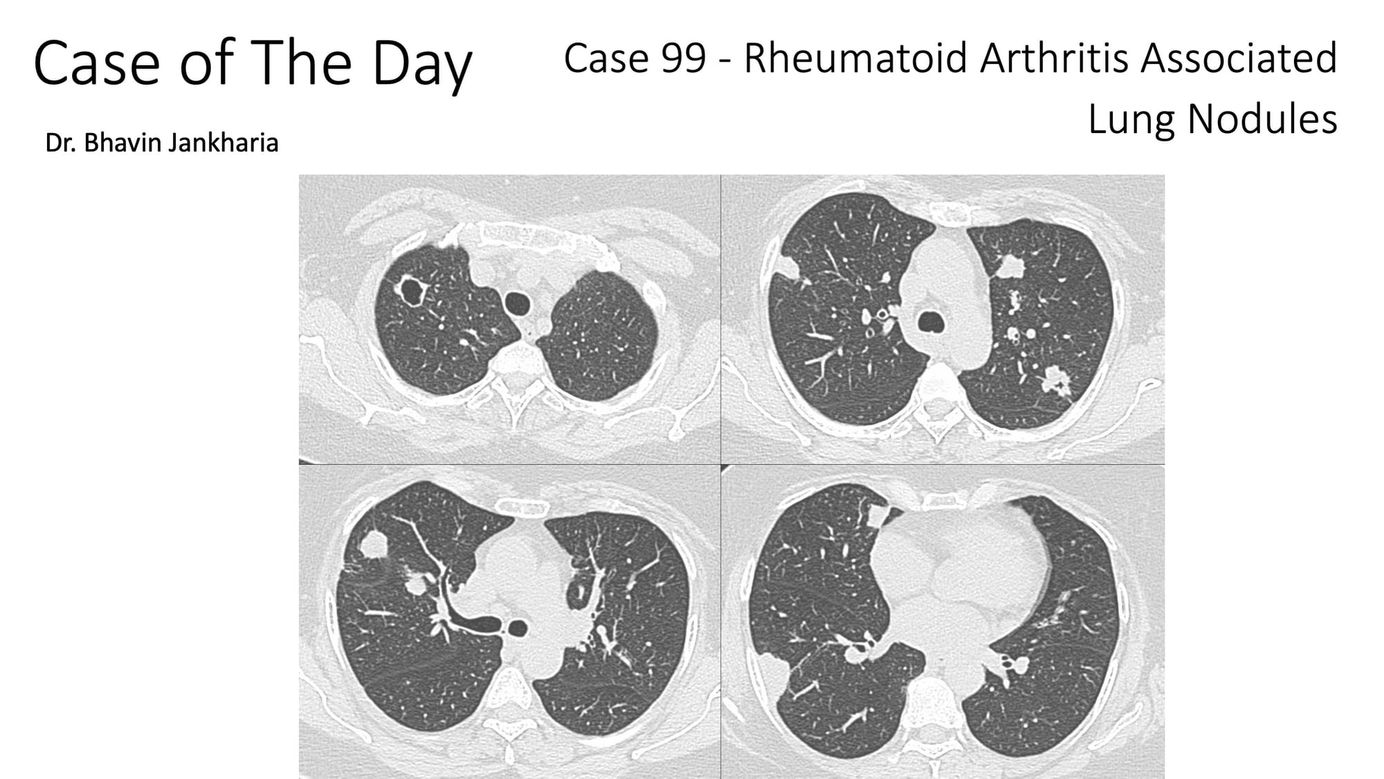

CT chest shows multiple varying sized lung nodules with a peribronchovascular distribution pattern.